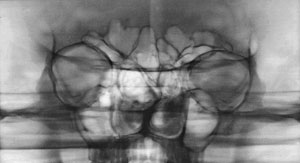

Лор-врачи после обзорных снимков

очень любят назначать зонограммы (Рис. 1.) и томограммы (Рис. 2 а, б.) лицевого

черепа. Это позволяет выделить интересующую область (например, пазухи) для детального

Зонограмма средней зоны пациента с

грубой деформацией лицевого черепа: гипертелоризмом, пороком формирования

полости носа.